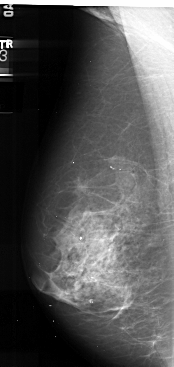

A_1035_1.LEFT_CC

LEFT_CC LINES 4936 PIXELS_PER_LINE 2446 BITS_PER_PIXEL 16 RESOLUTION 42 NON_OVERLAY